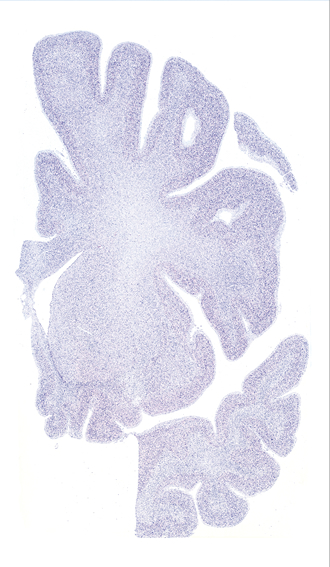

Hi-Resolution Sections · Cells (Nissl Staining) · Virtual Microscopy

Frontal sections (Nissl) from the Atlas Brain:

Slice ID:

r2-0221

Plate NR:

14

Position:

-10,4 mm